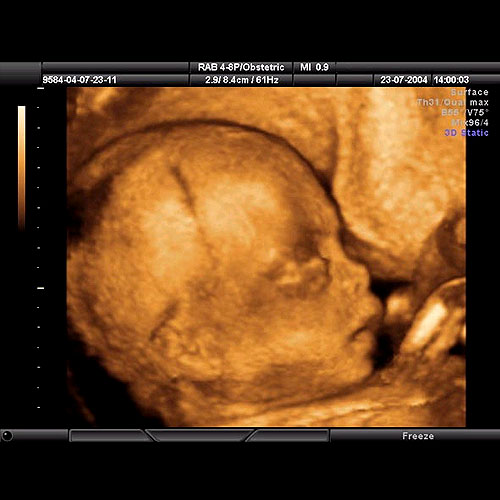

Ayrıca bünyemizde i̇nvitro laboratuvarı nın bir şubeside bulunmakta olup her.